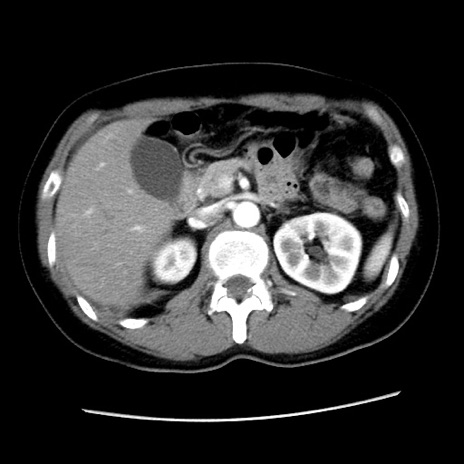

冠状断像

【症例】 50歳代女性

【主訴】 腹痛

【現病歴】前日生レバーを食べた。今朝に排便あり。 昼前に突然発症の腹痛を生じ、当院救急外来を受診した。

【既往歴】 子宮筋腫にてで子宮全摘後

【身体所見】 意識清明、腹部:平坦、軟、下腹部やや左を中心に圧痛・反跳痛あり、筋性防御あり

【データ】WBC 7800、CRP 0.07